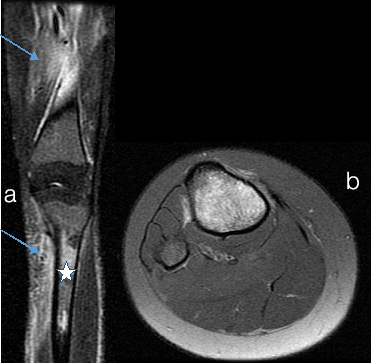

Osteomyelitis a) X-RAY LEFT LEG b)T1WI c)T2WI d)T1 fat sat + Gd

a) X-ray left leg shows multiple irregular cortical erosions in femur shaft and lower end. Extending into the medulla of femur (arrow in a). There is lamellated type of periosteal reaction.

b) and c) MRI T1WI Coronal show multiple cortical irregularities and erosions with medullary hyperintense signal in shaft and distal femur. There are multiple collections in surrounding soft tissues which appear hypointense on T1 and hyperintense on T2. (arrow in c). d) Contrast enhanced T1 fat sat image - shows enhancement in medulla and surrounding soft tissues